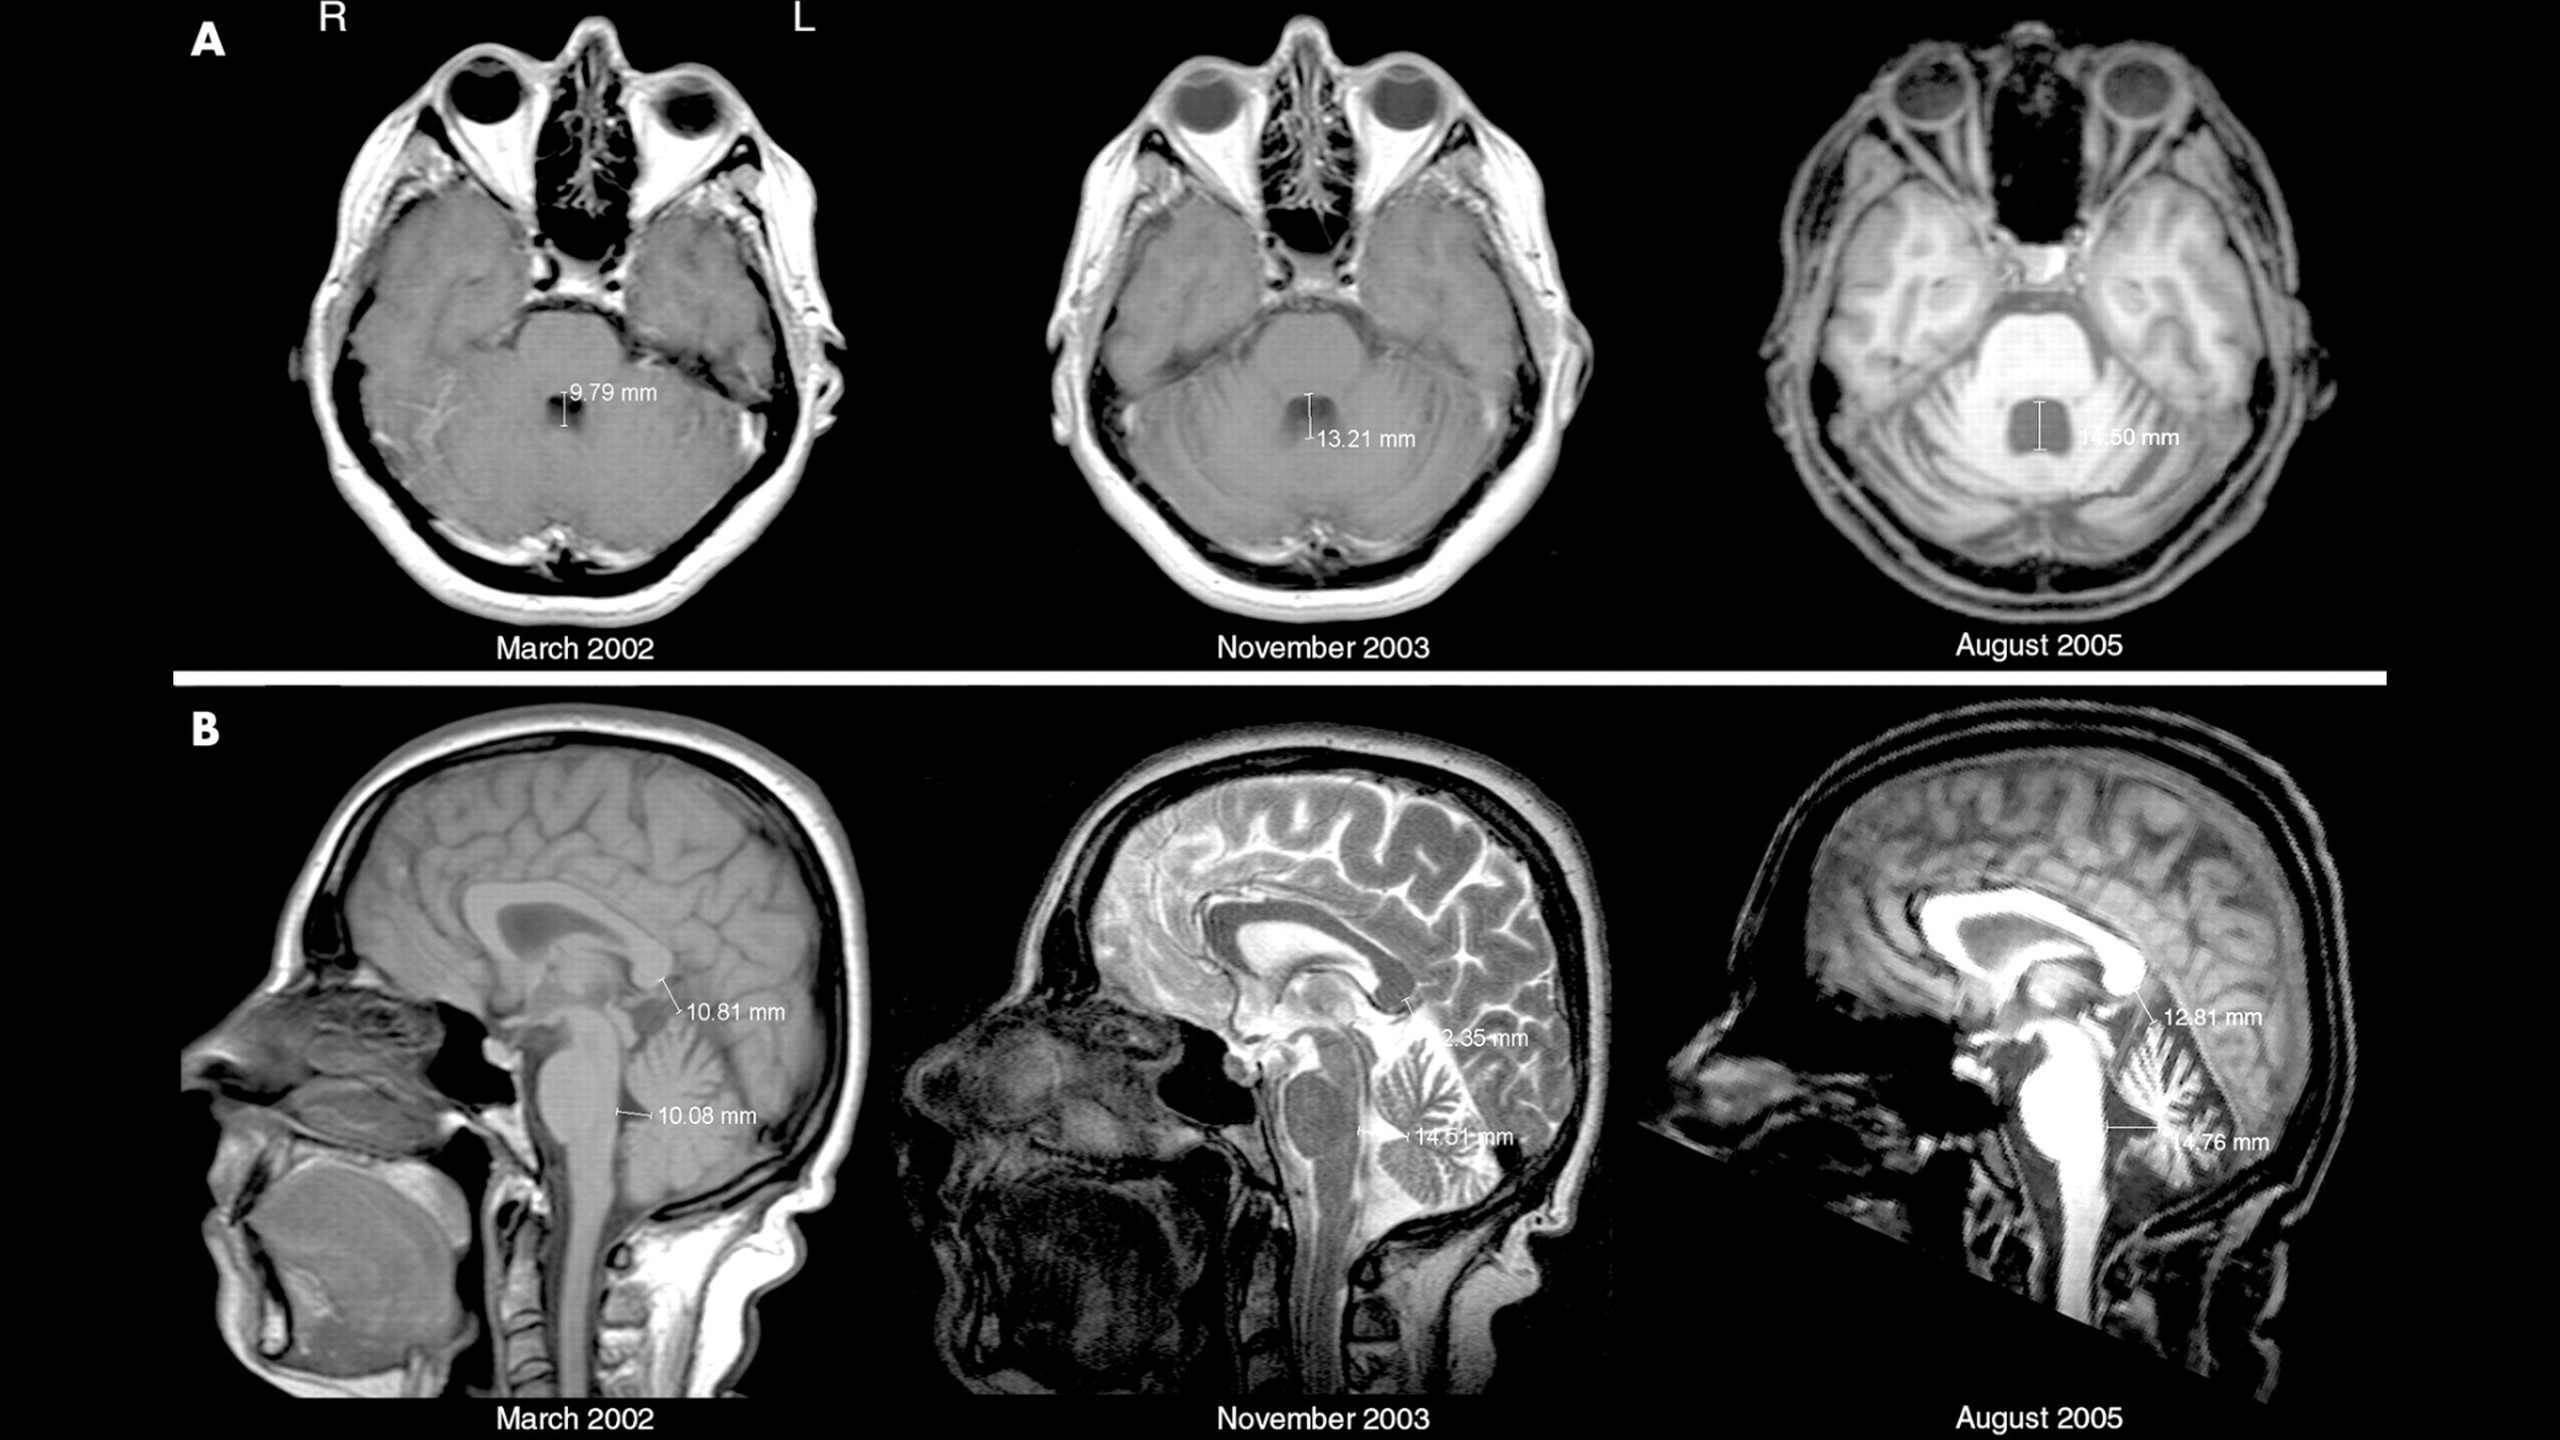

Khi có nghi ngờ thoái hóa tiểu não, bác sĩ sẽ tiến hành cho bệnh nhân chụp CT và MRI. Nếu có nghi ngờ viêm nhiễm ở tiểu não, bệnh nhân sẽ được làm xét nghiệm dịch não tủy. Bác sĩ cũng có thể cho bệnh nhân xét nghiệm tìm nồng độ của vitamin E, kháng thể chống ung thư như anti-Ri, anti-Yo,...